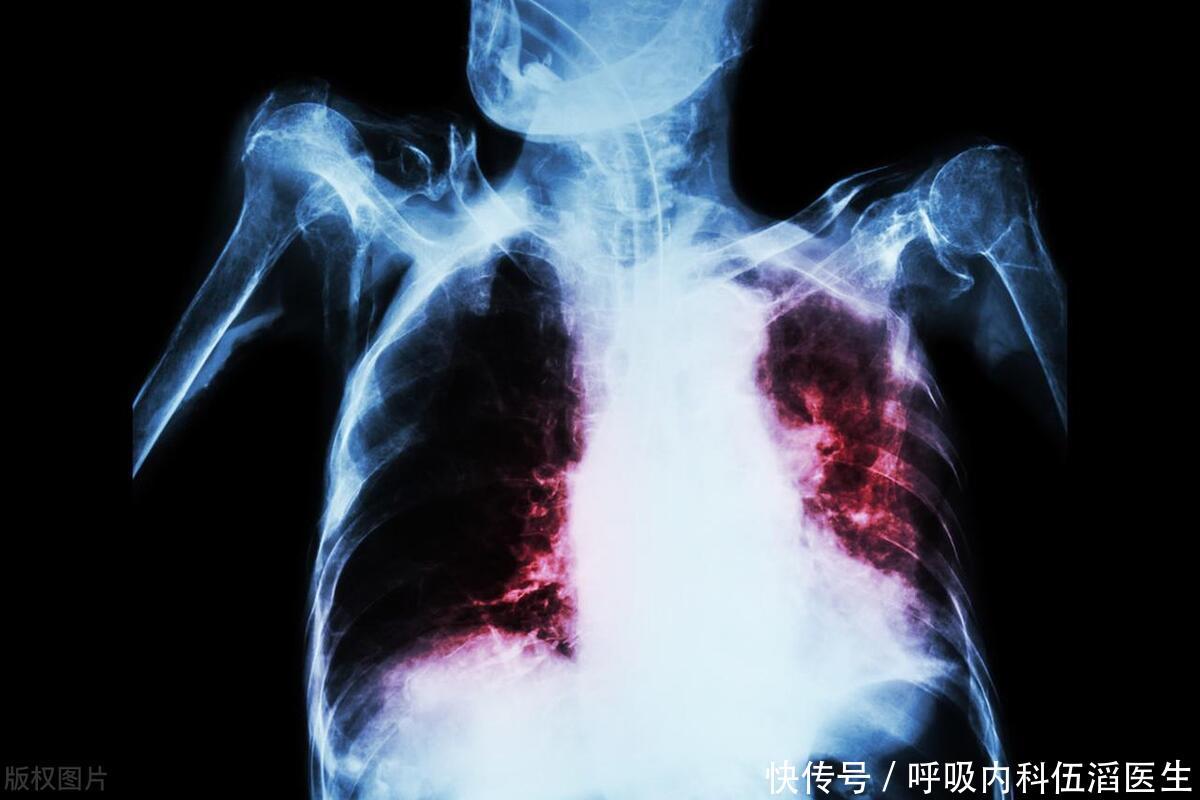

肺不好的人,身上这4处会“喊疼”,若没有,说明肺还算可以

肺部

炎症

肿瘤

肺癌

肺结核

慢性阻塞性肺疾病

胸腔积液

呼吸衰竭

支气管扩张